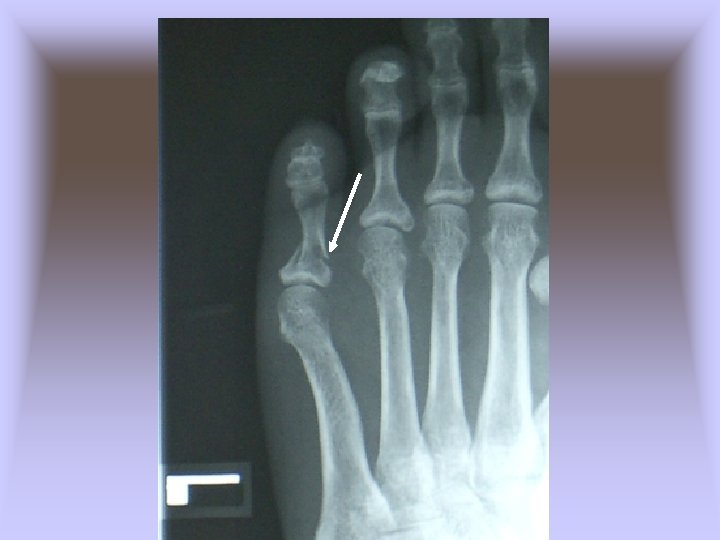

• Jones Fracture – Cause of Injury • Fracture of metatarsal caused by inversion or high velocity rotational forces • Most common = base of 5 th metatarsal – Sign of Injury • Immediate swelling, pain over 5 th metatarsal • May feel a “pop” • High nonunion rate and course of healing is unpredictable – Care • Generally requires 6 -8 weeks non-weight bearing with short leg cast if non-displaced • If nonunion occurs, internal fixation may be required

Case 1 Lisfranc Injury • Lisfranc injury • 1% of orthopedic trauma • 20% missed on initial presentation • Named for Jacques Lisfranc who was a surgeon in Napoleon’s army in the early 1800’s.

Case 1 Lisfranc Injury • Lisfranc joint – Stable axis of rotation – Keystone for plantar and dorsiflexion – Horizontal axis through second MT – Plantar flexion with an axial load provides stress to dorsally displace 2 nd MT base